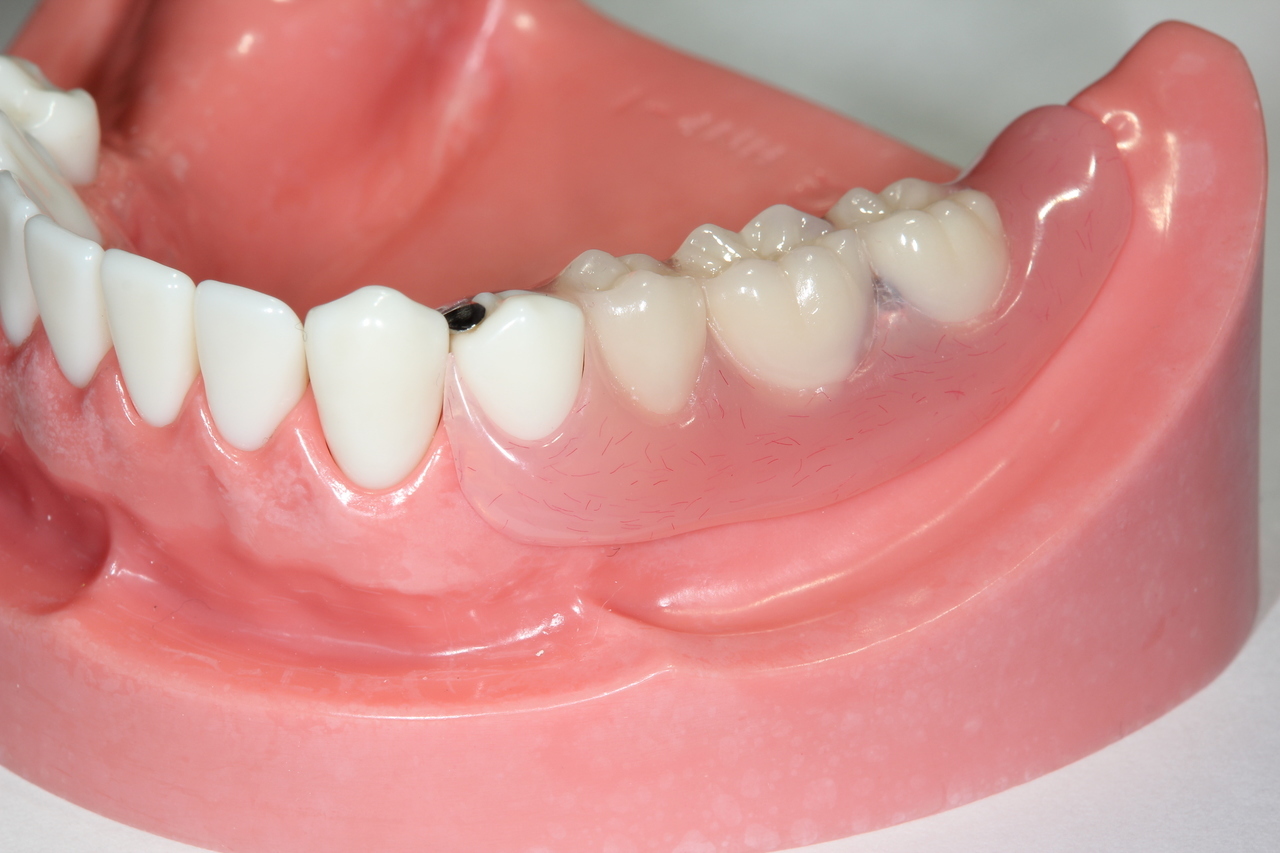

奥歯インプラント(スクリュー固定)

(伊東市 女性)

治療の流れ

むし歯で歯を失ってしまいました。

インプラントを埋入し、最終的な被せ物を装着しました。(ネジ穴をふさぐ前)

ネジ穴をふさぐとこの様な状態になります。